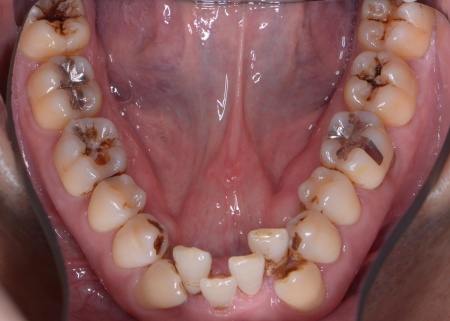

拝見したところ、上下の歯は、ずれたりねじれたりしてデコボコに生えており、著しく歯並びが乱れていました。

さらに、左下奥歯は重度の歯周病であり、歯を支えている骨が一部溶けていることが判明しました。

・歯の表面に小さなボタン状の装置であるブラケットを接着し、そこにワイヤーを通して歯を動かす「マルチブラケット矯正」を行う

その後、上下の歯の表面にブラケットを接着し、上顎にはトランスパラタルアーチを、下顎にはミニインプラントを使用しながら、マルチブラケット矯正を開始しました。